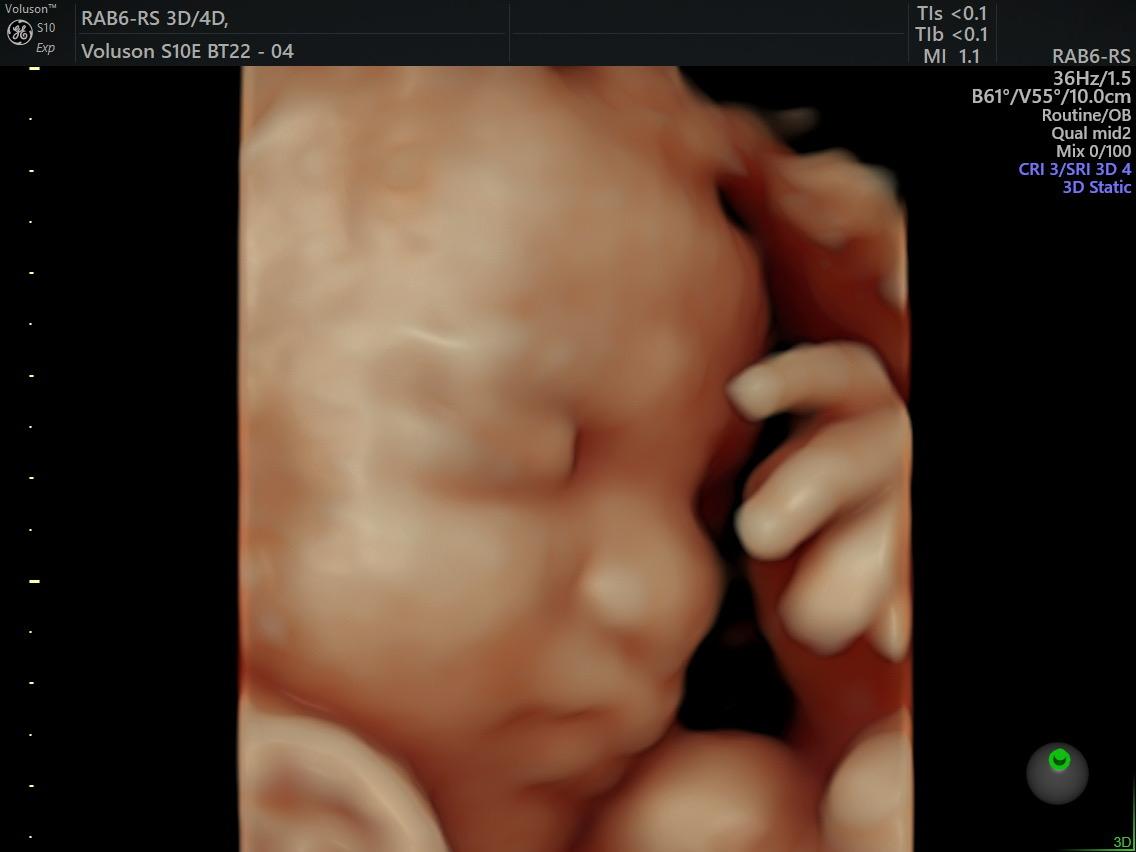

Fetal Medicine

Ultra Sound

Gallery

Images

Photos